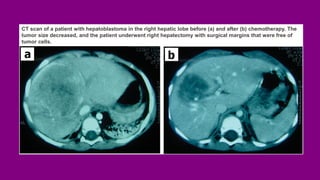

CT scan of a patient with hepatoblastoma in the right hepatic lobe before (a) and after (b) chemotherapy. The

tumor size decreased, and the patient underwent right hepatectomy with surgical margins that were free of

tumor cells.

CT scan ofa patient with hepatoblastoma in the right hepatic lobe before (a) and after (b) chemotherapy. The tumor size decreased, and the patient underwent right hepatectomy with surgical margins that were free of tumor cells.